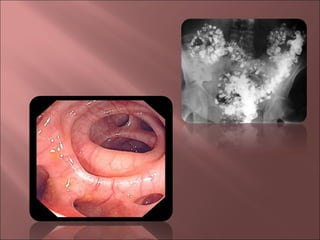

   Estudios con bario.

   Colonoscopia.

   Sigmoidoscopia.

   Tomografía computarizada.

   Colonoscopia: Excluir neoplasia

   Colonoscopia